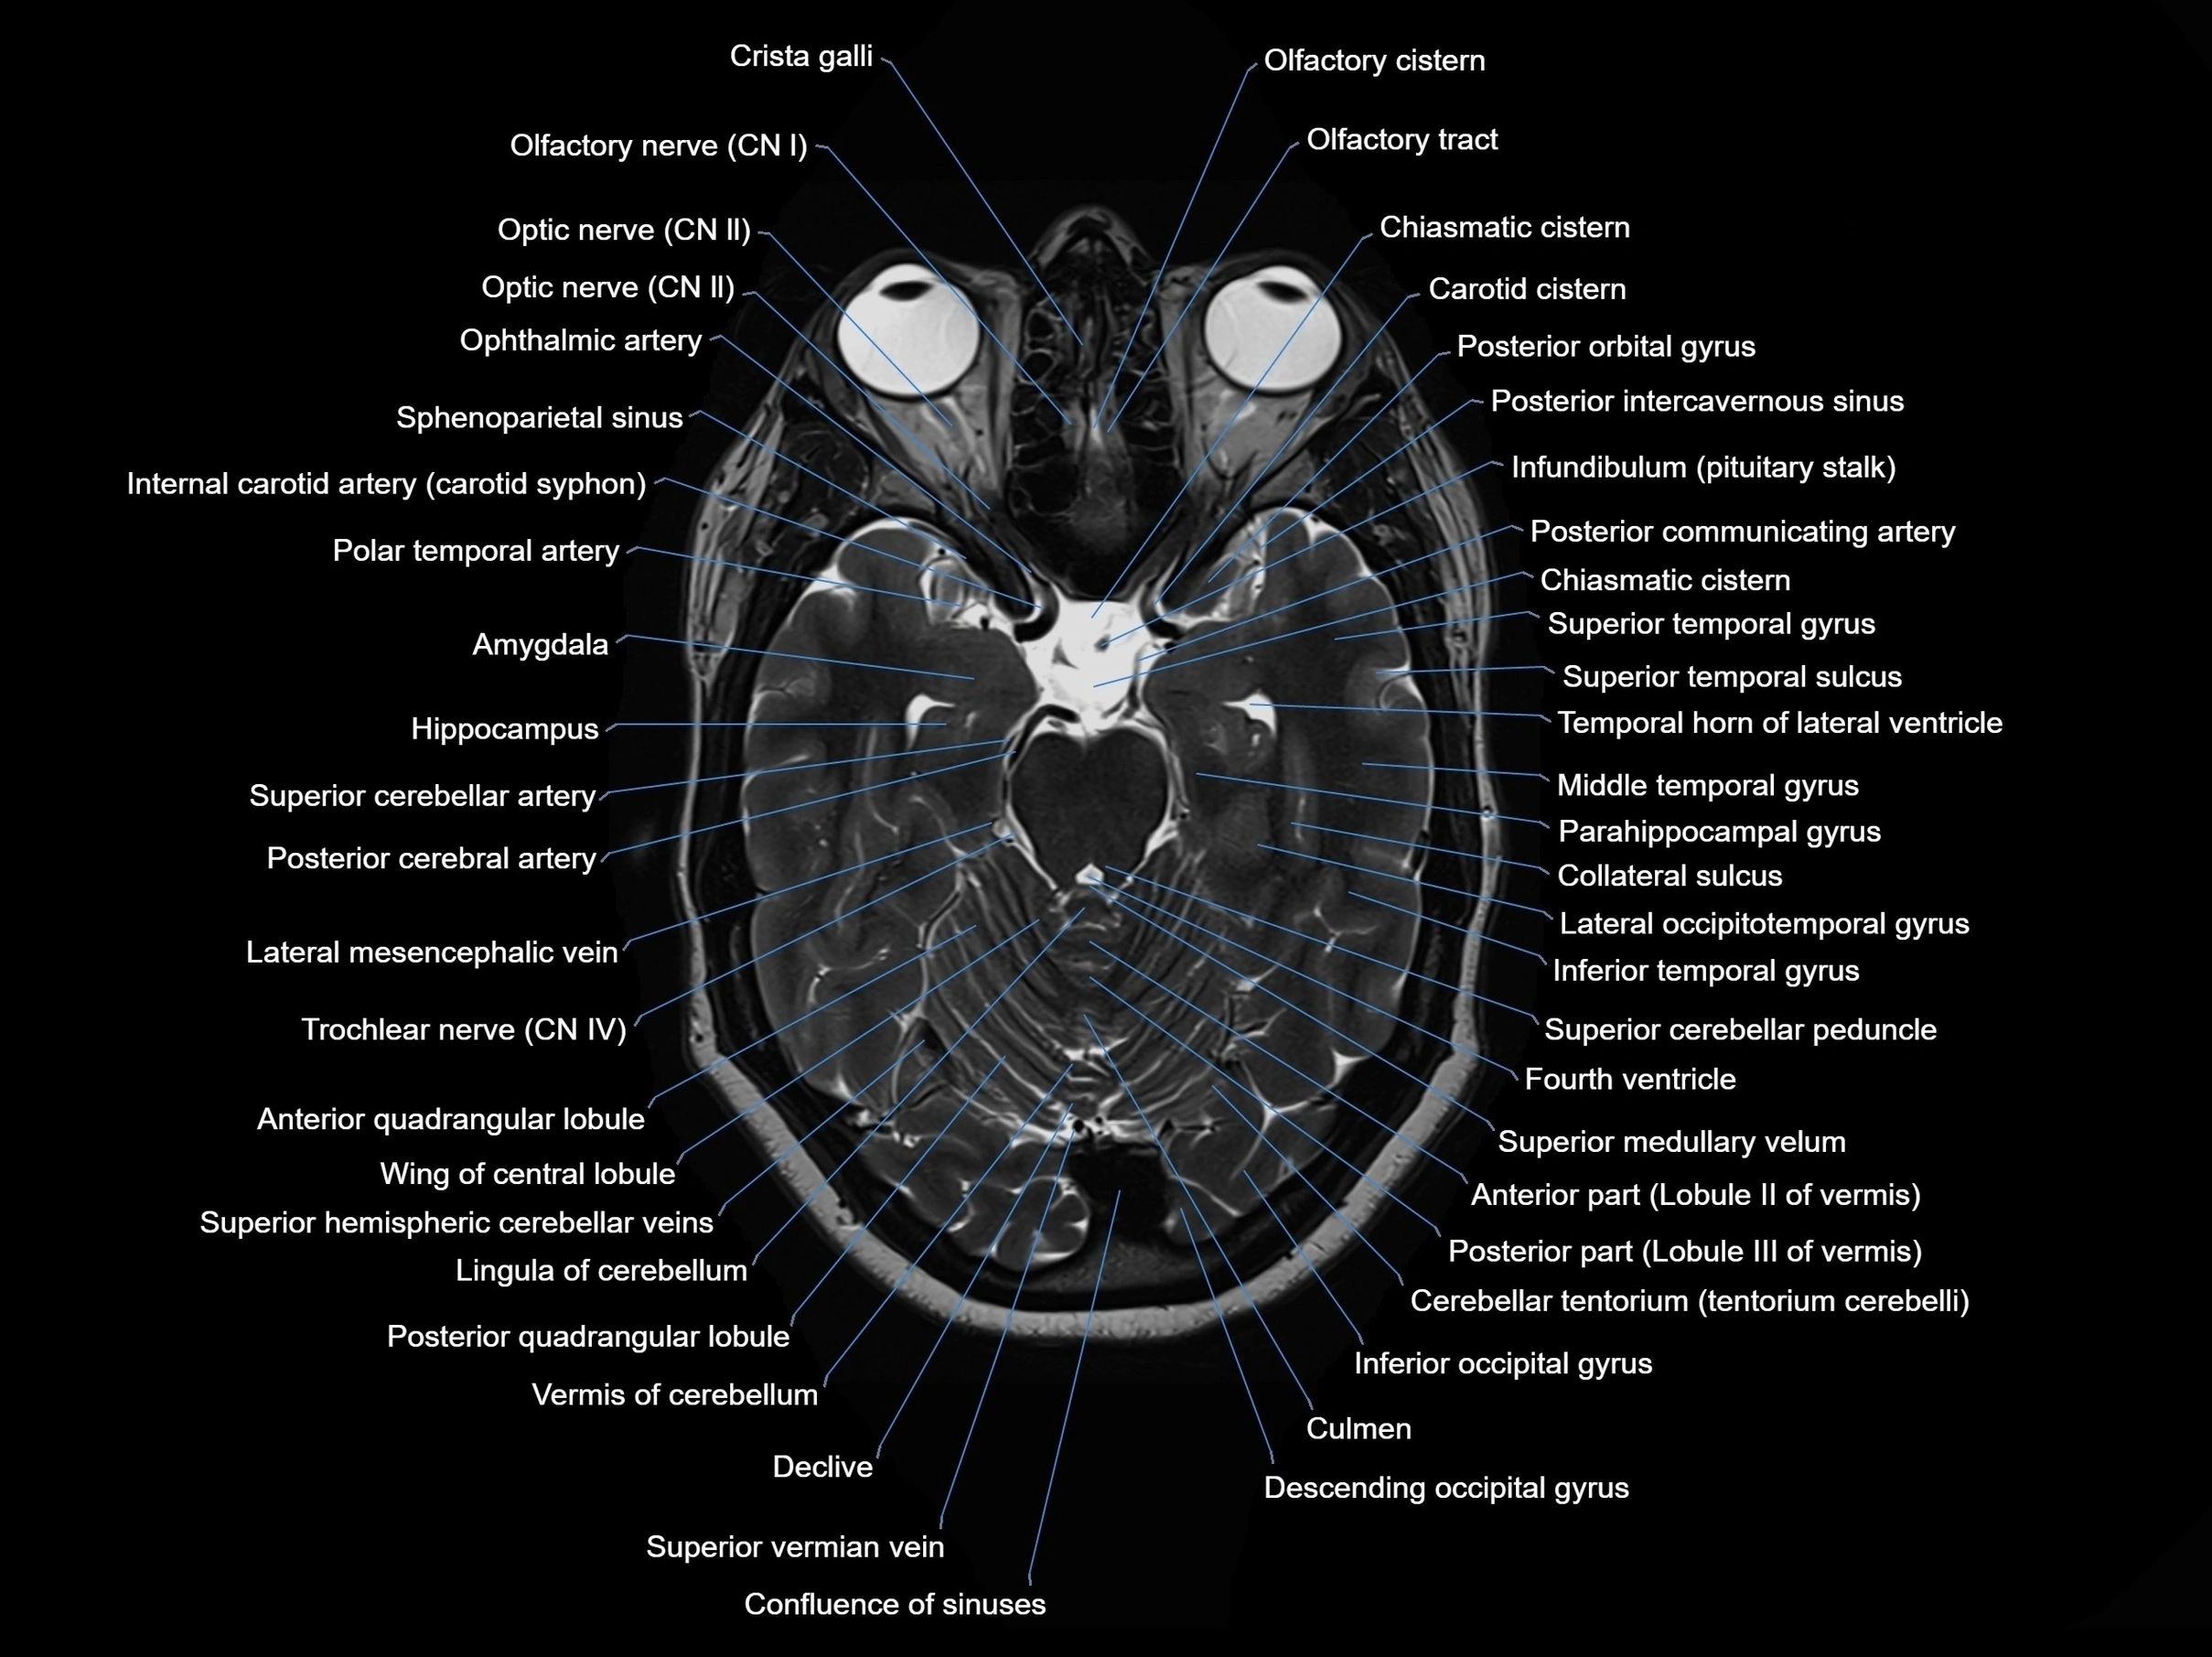

MRI images